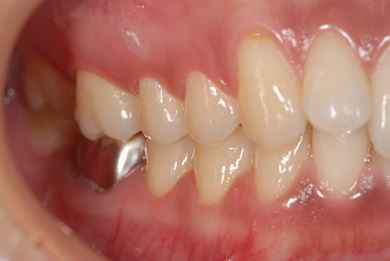

インプラントの症例写真 IMPLANT

インプラント治療

| 主訴 | 銀歯がはずれた奥歯にひびが入っており、抜歯しなければいけないため、インプラントの治療相談を希望。 | ||||||||||||||||||||||||||||||||

| 治療内容 | インプラント1本、メタルボンドセラミック1本 | ||||||||||||||||||||||||||||||||